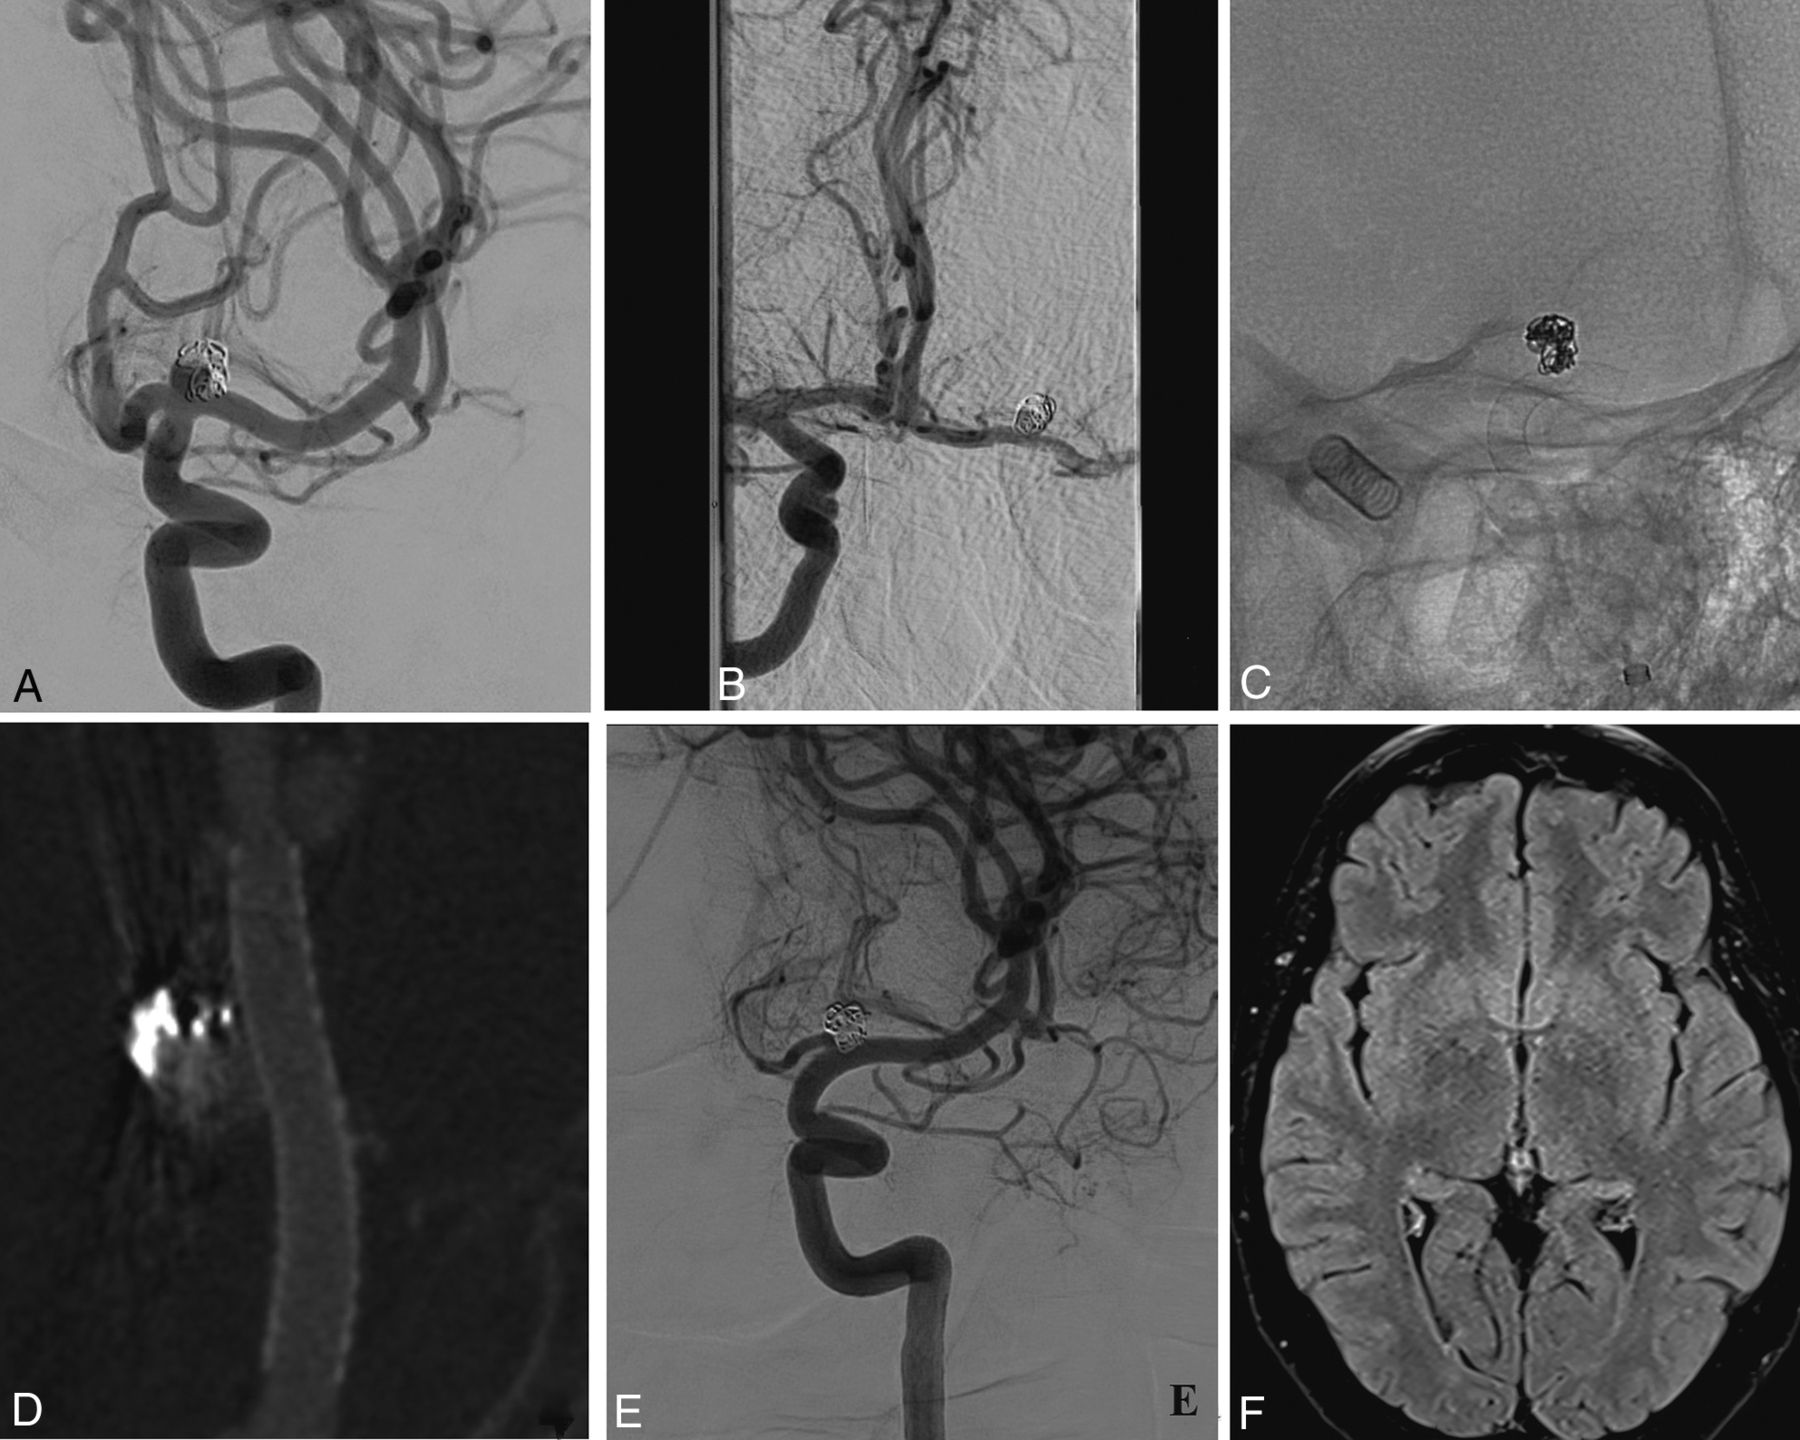

Patient 8. A, The left ICA (frontal view) depicts a previously ruptured and recanalized medium-sized ICAbifA treated with coiling during the acute phase. B, The presence of contralateral filling from the AcomA. C, A PED, 3.5 × 12 mm, is successfully deployed covering the aneurysm and the left A1 segment. The PED was delivered before the origin of the M1 lenticulostriate arteries. D, Flat panel angiography confirms good vessel wall apposition of the stent. E, A 14-month angiographic follow-up shows complete aneurysm occlusion as well as flow remodeling of the covered A1 with narrowing but without any lesions on the FLAIR sequences (F).